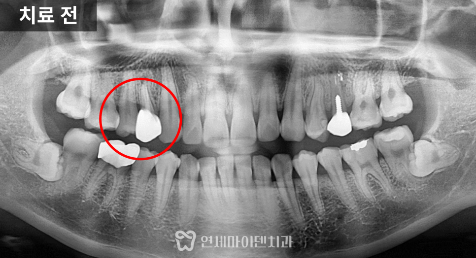

이번에 소개할 케이스는

과거 신경치료를 받은 후 불편감과

염증이 있는 경우입니다.

재신경치료를 통해 치아를

보존할 수 있었던 사례입니다.

해당 치아는 과거 신경치료와

크라운을 한 상태였습니다.

신경치료 후 불편함이 계속되었고

뿌리 끝에 염증이 있었습니다.